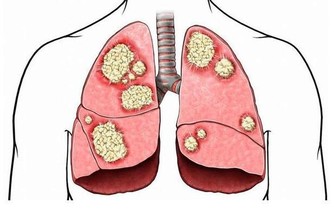

2、肺部感染是腦梗塞病人最常見的並發症。有很多研究表明,肺部感染成為腦梗塞的最主要的致死因素。腦梗塞病人的肺部感染一般與以下因素有關病人長期臥床,產生的沉積性肺炎,因此,在護理工作中,提倡勤翻身,勤吸痰。照顧不當,引起病人飲水或飲食嗆咳而引發的戲入性肺炎。病人使用抗生素不當,造成菌群失調,加上病人多為老年、抵抗力差,也增加了易感因素。